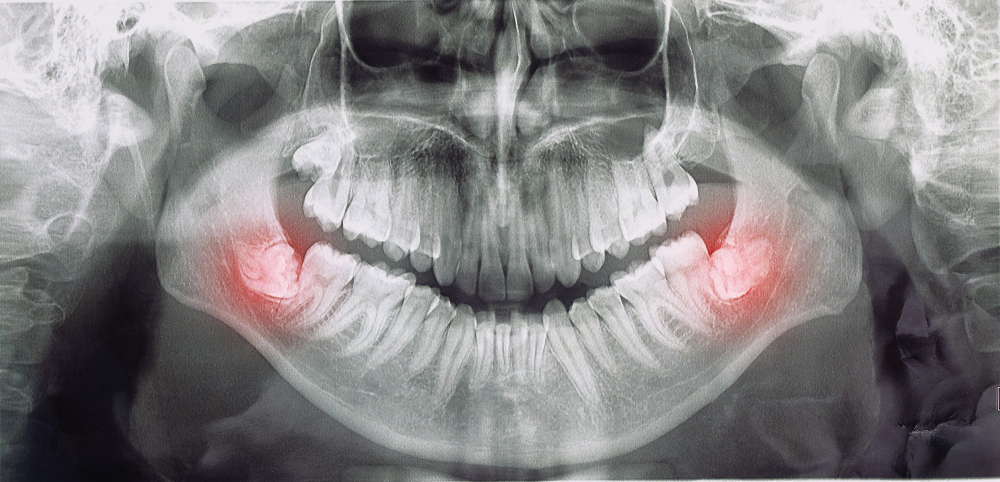

Denti del giudizio: quando toglierli?

I terzi molari, chiamati anche denti del giudizio, solitamente fuoriescono dal sistema osso/gengiva in un’età compresa tra i 17 e i 25 anni.

Si tratta di quattro denti che si dividono tra l’arcata superiore e quella inferiore.